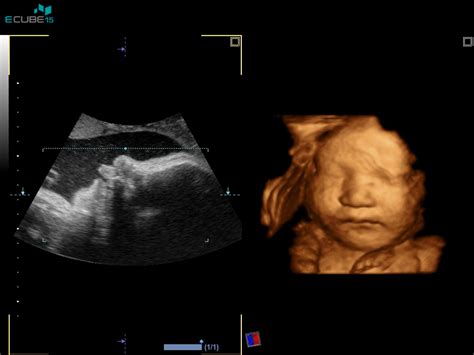

Ultrazvok v 22. Tednu Nosečnosti

Zdaj ko so otrokove oči in ustnice že bolj razvite, je otroček že bolj podoben novorojenčku. Če še nisi imela ultrazvoka na sredini nosečnosti, je ta teden kot nalašč za to. Ultrazvok v starosti od 18 do 22 tednov omogoča vpogled v vse otrokove glavne organe in ostale dele telesa. Med tem pregledom zdravnik preveri anatomijo ploda, oceni rast in razvoj ter preveri količino plodovnice in stanje posteljice. To je tudi čas, ko se opravi še preostanek genetskega testiranja, če je bilo potrebno. Ultrazvočni pregled v 22. tednu je ključen za potrditev, da se otrok pravilno razvija in je zdrav.